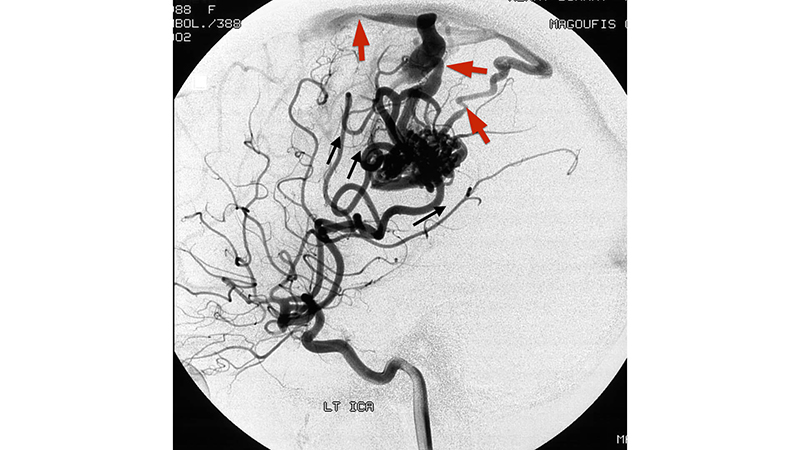

- Πλάγια λήψη εγχύσεως στην αριστερή έσω καρωτίδα. Διακρίνονται οι τρείς κύριοι τροφοφόροι κλάδοι που αρδεύουν της αρτηριοφλεβώδη φωλεά (μαύρα βέλη). Η φλεβική παροχέτευση γίνεται μέσω διατεταμένων βρεγματικών φλεβών προς τον άνω οβελιαίο κόλπο. Βλέπουμε τις εστιακές στενώσεις στο φλεβικό σκέλος που ευθύνονται γιά την αύξηση της πιέσεως μέσα στην φωλεά και γιά την αιμορραγία (κόκκινα βέλη).